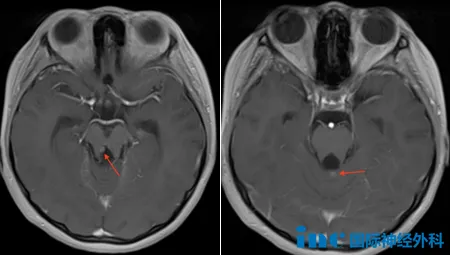

10岁男性患儿安格2025年4月出现呕吐症状,初诊怀疑胃肠道问题。6月MRI检查发现后颅窝存在3.1cm×3.6cm×5.0cm肿瘤,肿瘤占据第四脑室并阻塞脑脊液通道,引发脑积水。当月接受内镜下第三脑室造瘘术(ETV),4天后后行后颅窝开颅手术,实现内镜下肿瘤全切。术后恢复良好,仅存右侧眼球内收受限,可正常行走活动。

术后病理显示为罕见低级别胶质瘤,基因检测显示GFAP、Olig2、ATRX和SOX10阳性,H3K27M、p53和BRAF600E阴性。甲基化亚型分析表明该肿瘤无法归类于现有数据库任何已知类型。2026年1月复查发现小脑蚓部、右侧导水管周围区域和内侧中脑存在小型结节,提示肿瘤复发或转移可能。

Rutka教授分析认为,右脑室周围和小脑蚓部结节可能为原发肿瘤残留,若双侧侧脑室结节确存在,则提示肿瘤转移。因当前结节体积较小,建议先行脊髓MRI检查明确肿瘤扩散情况。